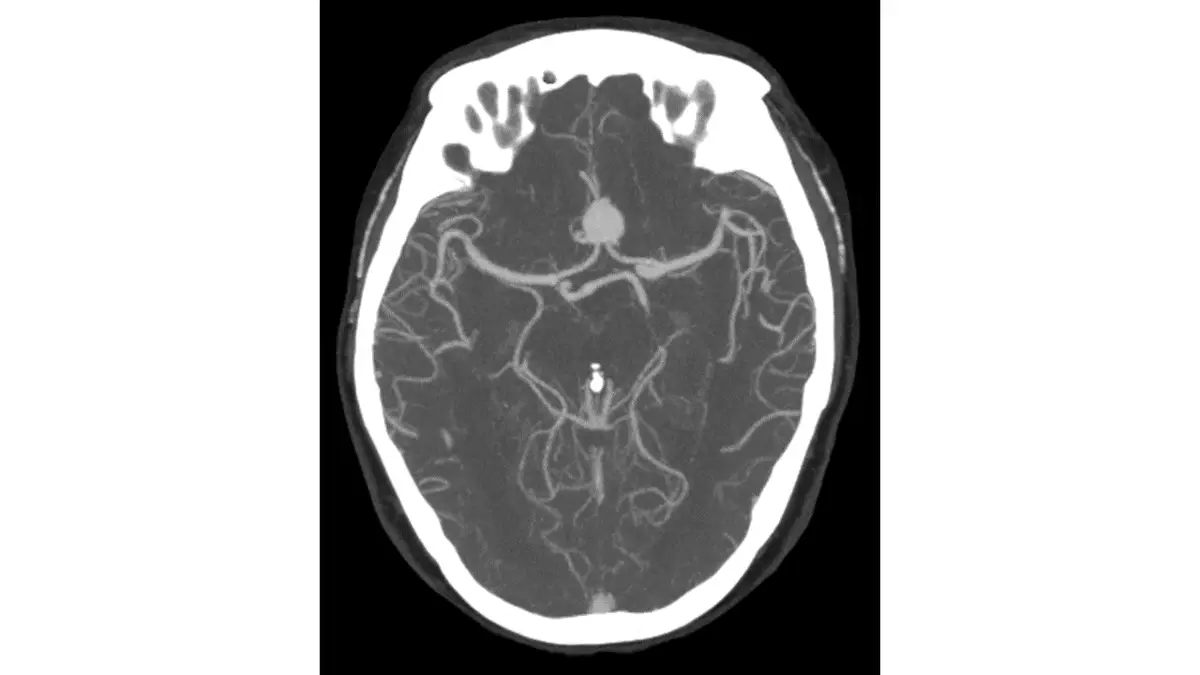

頭部電腦斷層血管攝影呈現如下圖,下列有關影像重組那一項最正確?

頭部電腦斷層血管攝影(CT angiography, CTA)在取得原始斷層資料後,可透過多種**影像重組(image reconstruction)**技術呈現血管結構。本題考查各重組方式的特性及其典型外觀,尤其是最大密度投影(maximum intensity projection, MIP)的識別。

圖示為頭部 CTA 的**軸向(axial)**斷層影像:

- 背景呈純黑色

- 腦部血管(動脈及分支)呈現亮白色細線狀結構,遍布整個腦部橫斷面

- 可見 Willis 環(circle of Willis)的主要分支、大腦前動脈、大腦中動脈、大腦後動脈等

- 骨骼結構(顱骨)顯示為白色外框,腦實質呈均勻灰色背景

- 血管細節清晰,可見末梢小血管分支

- 整體呈現為2D 投影影像,血管在所有深度中均同時呈現(無立體感),具有「將最高密度值投影到平面」的特徵

此外觀為**最大密度投影(MIP)的典型呈現:沿投影方向選取每條射線上密度值最高的體素(voxel)**投影到影像平面,使含碘造影劑的高密度血管突出顯示,背景組織被抑制。